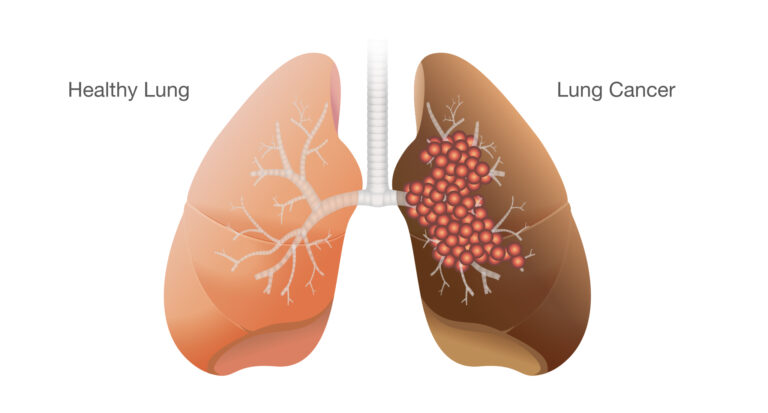

Lung cancer is a serious medical condition in which abnormal cells grow uncontrollably in the tissues of the lungs. These abnormal cells form tumors that interfere with the normal function of the lungs, reducing the body’s ability to receive oxygen and remove carbon dioxide efficiently. Lung cancer is one of the most commonly diagnosed cancers worldwide and remains a leading cause of cancer-related deaths, largely due to late diagnosis and lack of early symptoms.

Lung cancer begins when genetic changes occur in the cells lining the airways or lung tissue. These changes cause cells to grow uncontrollably instead of following the normal cycle of growth and death. Over time, these abnormal cells accumulate and form a tumor.

As the tumor grows, it may block air passages, invade surrounding tissues, or spread to nearby lymph nodes and distant organs through the bloodstream or lymphatic system. This ability to spread, known as metastasis, makes lung cancer particularly challenging to treat if not detected early.